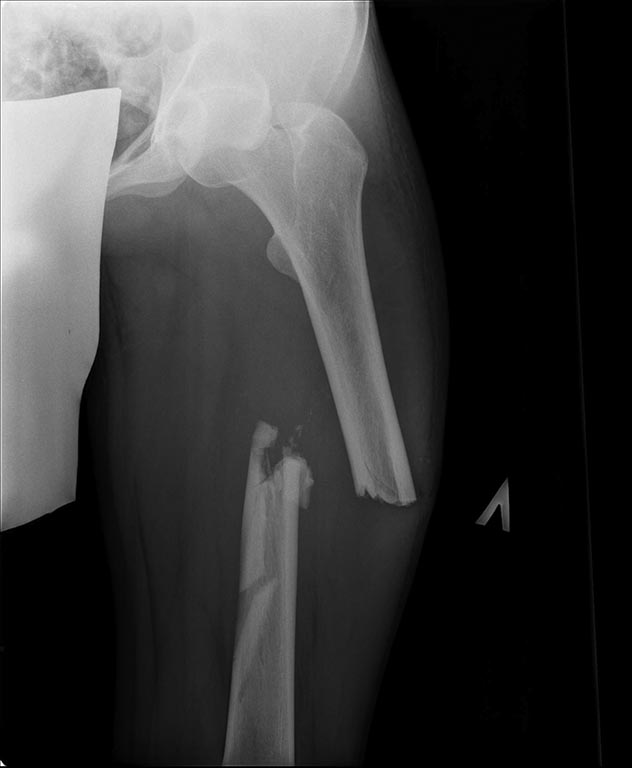

Добрый день уважаемые коллеги. Вашему вниманию представляю

пациента(мужчина, 30 лет).

Тяжелая сочетанная травма 7 мес. назад. Из скелетной травмы: открытый

перелом бедра, открытый перелом дистального метаэпифиза левого плеча,

закрытый перелом шейки левого плеча). Все повреждения были

прооперированы.Бедро синтезировано штифтом Остеомед d-11мм.

Раны зажили первично. Пациент после выписки впервые появился на

контрольный осмотр ч/з 7 месяцев. Жалобы на боли в левом бедре при

нагрузке, ощущение подвижности в месте перелома.